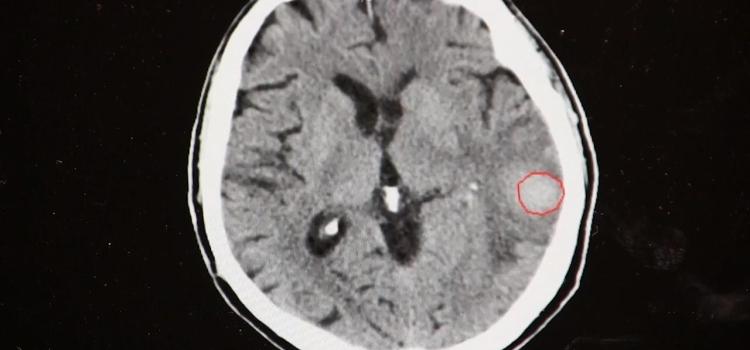

Artificial intelligence (AI) has found a unique niche to help automate the activation of acute care teams for pulmonary ...